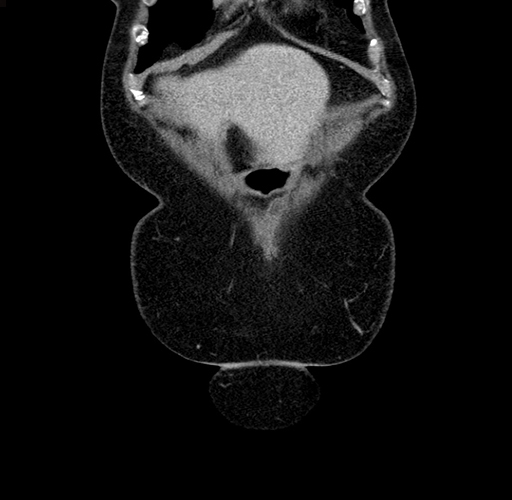

Pre-Chemo: Coronal Venous

Coronal Venous